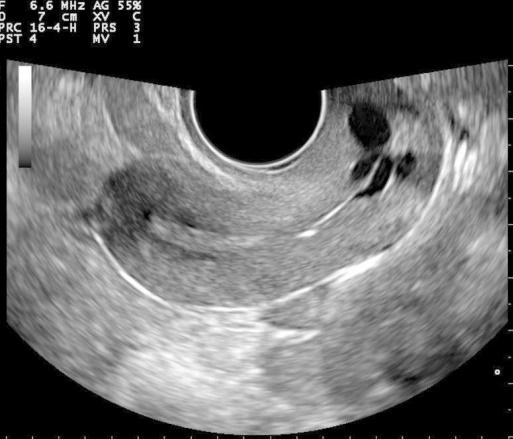

Hidrosálpinx

Es

una acumulación de fluido en la trompa de falopio.

Puede ser causado por

una obstrucción debido a acumulación de secreciones o fluido como consecuencia de PID o endometriosis entre otras cosas.

Sonográficamente observamos

la trompa dilatada, llena de fluido las paredes se observan finas, la masa tiene una apariencia multicisistica y usualmente es bilateral.